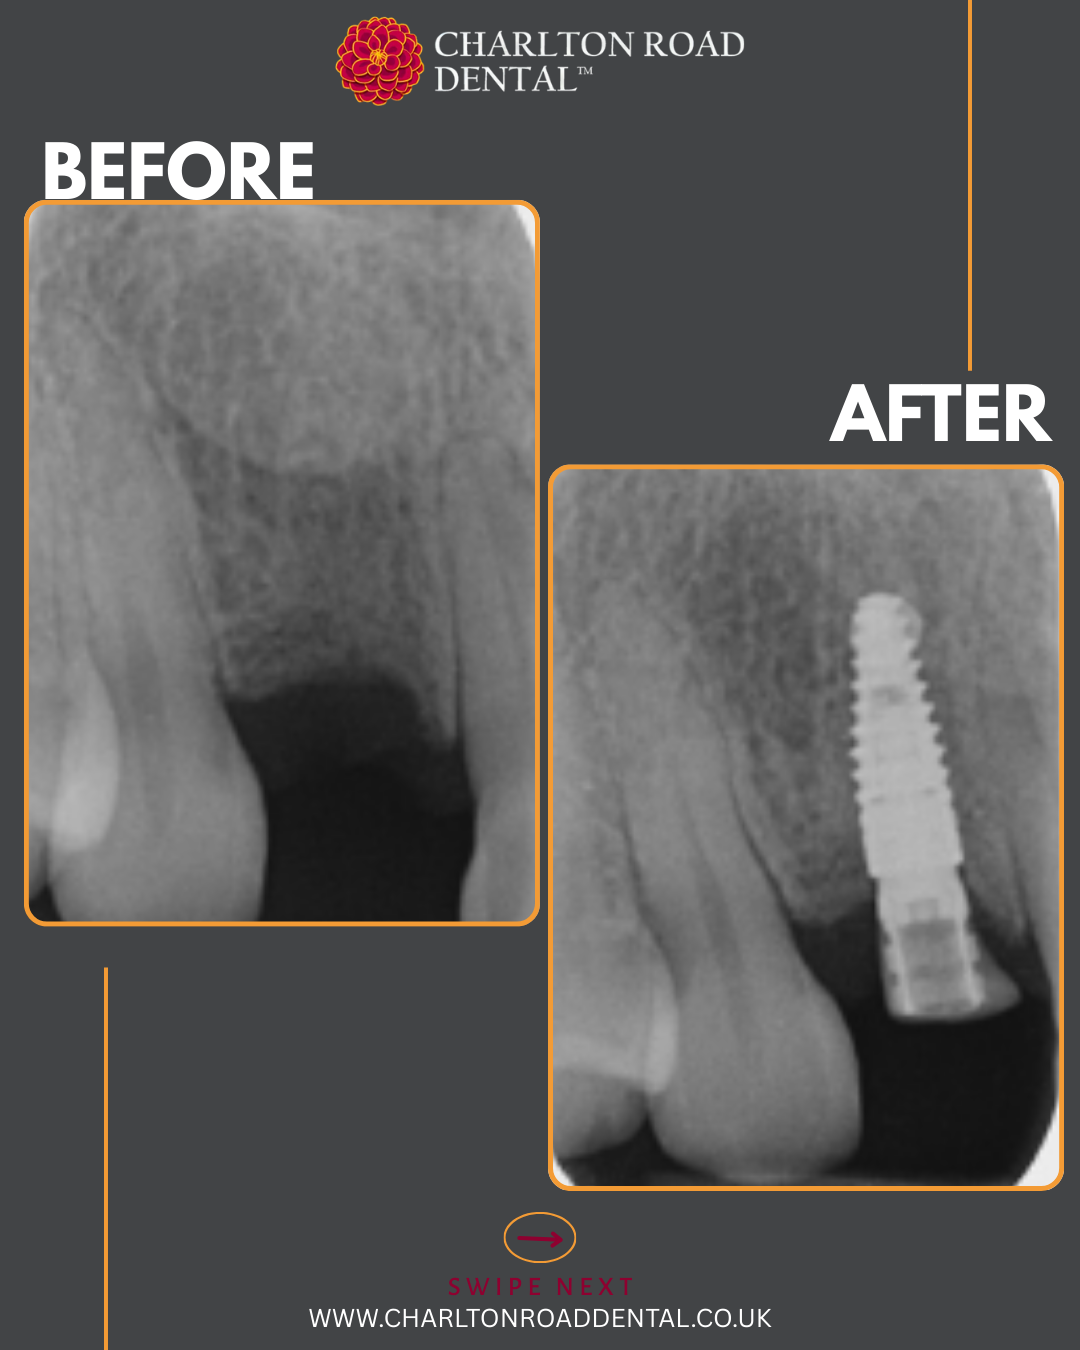

A week of implants @ Charlton Road Dental